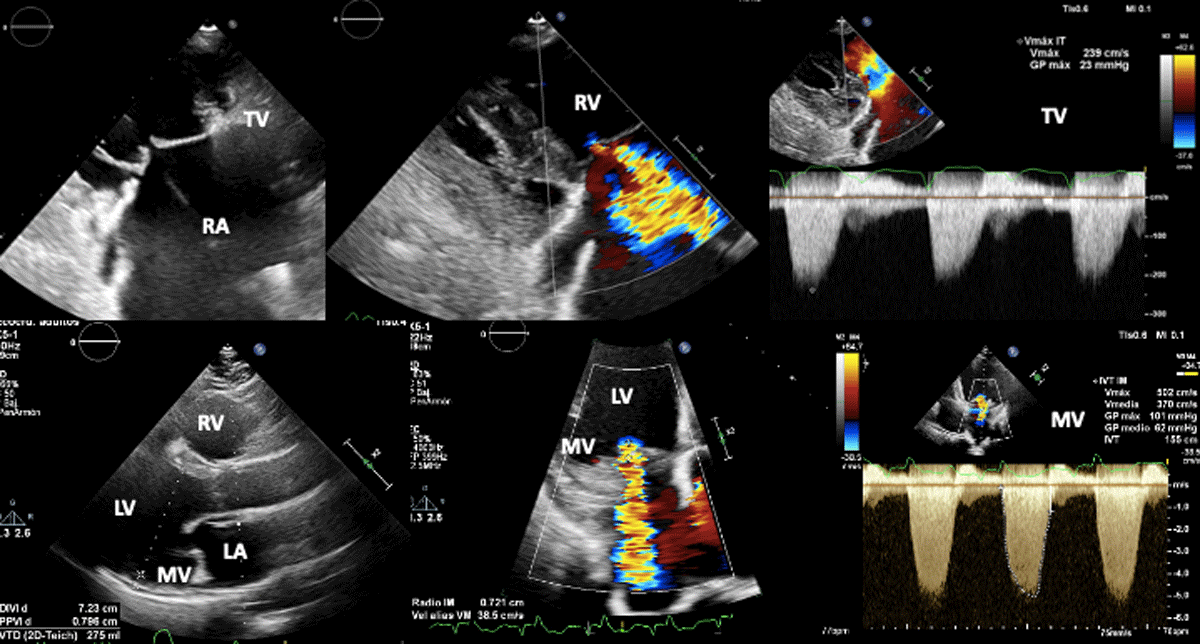

Figure 5

Biventricular dysfunction in a patient with Chagas disease. Superior figures show non coaptation of the tricuspid valve (due to right ventricular dilation) and its consequent functional regurgitation. Lower figures show mitral regurgitation secondary to left ventricular dysfunction.

Image: Mariana Corneli. Reproduced with permission of the photographer.